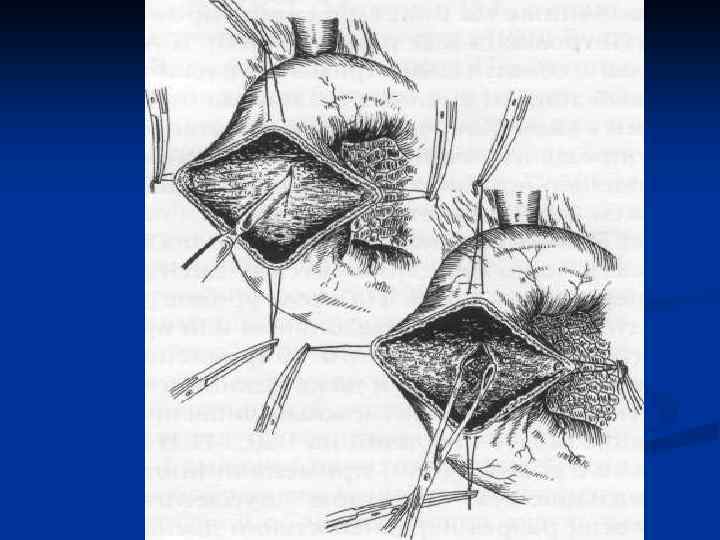

I. Восстановительные операции (восстановление проходимости протоков) 1. Эндобилиарные вмешательства под УЗИ или R – контролем (бужирование, баллонная дилатация, стентирование протоков). 2. Пластика стриктуры 3. Иссечение стриктуры с наложением анастомоза. II. Реконструктивные операции (наложение билиодигестивных анастомозов) 1. Анастомозы внепеченочных желчных протоков: а) с двенадцатиперстной кишкой (ХДА) б) с тощей кишкой (гепатико-, холедохоеюноанастомозы по Ру или по Брауну). 2. Анастомозы внутрипеченочных желчных протоков с сегментом тощей кишки, выключенной по Ру или желудком при высоких стриктурах

I. Восстановительные операции (восстановление проходимости протоков) 1. Эндобилиарные вмешательства под УЗИ или R – контролем (бужирование, баллонная дилатация, стентирование протоков). 2. Пластика стриктуры 3. Иссечение стриктуры с наложением анастомоза. II. Реконструктивные операции (наложение билиодигестивных анастомозов) 1. Анастомозы внепеченочных желчных протоков: а) с двенадцатиперстной кишкой (ХДА) б) с тощей кишкой (гепатико-, холедохоеюноанастомозы по Ру или по Брауну). 2. Анастомозы внутрипеченочных желчных протоков с сегментом тощей кишки, выключенной по Ру или желудком при высоких стриктурах